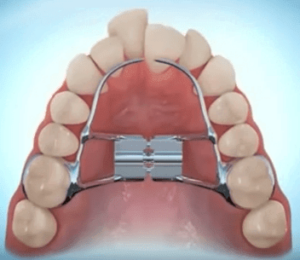

¿Qué tipo de ortodoncia se utiliza en niños?

La ortodoncia funcional es muy amplia. Existe una gran variedad de aparatos dependiendo del tipo de tratamiento que requiere cada paciente. Aunque la ortopedia funcional puede mejorar el alineamiento dental, no es su función principal, ya que éste se realiza mucho más eficazmente con los aparatos fijos (brackets).

CARACTERÍSTICAS PRINCIPALES DE LA ORTOPEDIA FUNCIONAL

La ortopedia funcional tiene el objetivo de corregir la disarmonía ósea de los maxilares. La mayoría de estos aparatos de ortodoncia funcional son removibles, de “quita y pon”, compatibles con la rutina diaria.

Dependiendo de su diseño:

Estimulan el crecimiento mandibular y frenan el crecimiento del maxilar superior: indicado en casos de dientes superiores prominentes y mandíbulas pequeñas.

Expansionan el maxilar superior: indicado en casos de compresión del maxilar y mordida cruzada.

Estimulan el avance del maxilar superior y frenan el crecimiento mandibular: indicado en casos de dientes inferiores prominentes y maxilar superior pequeño.